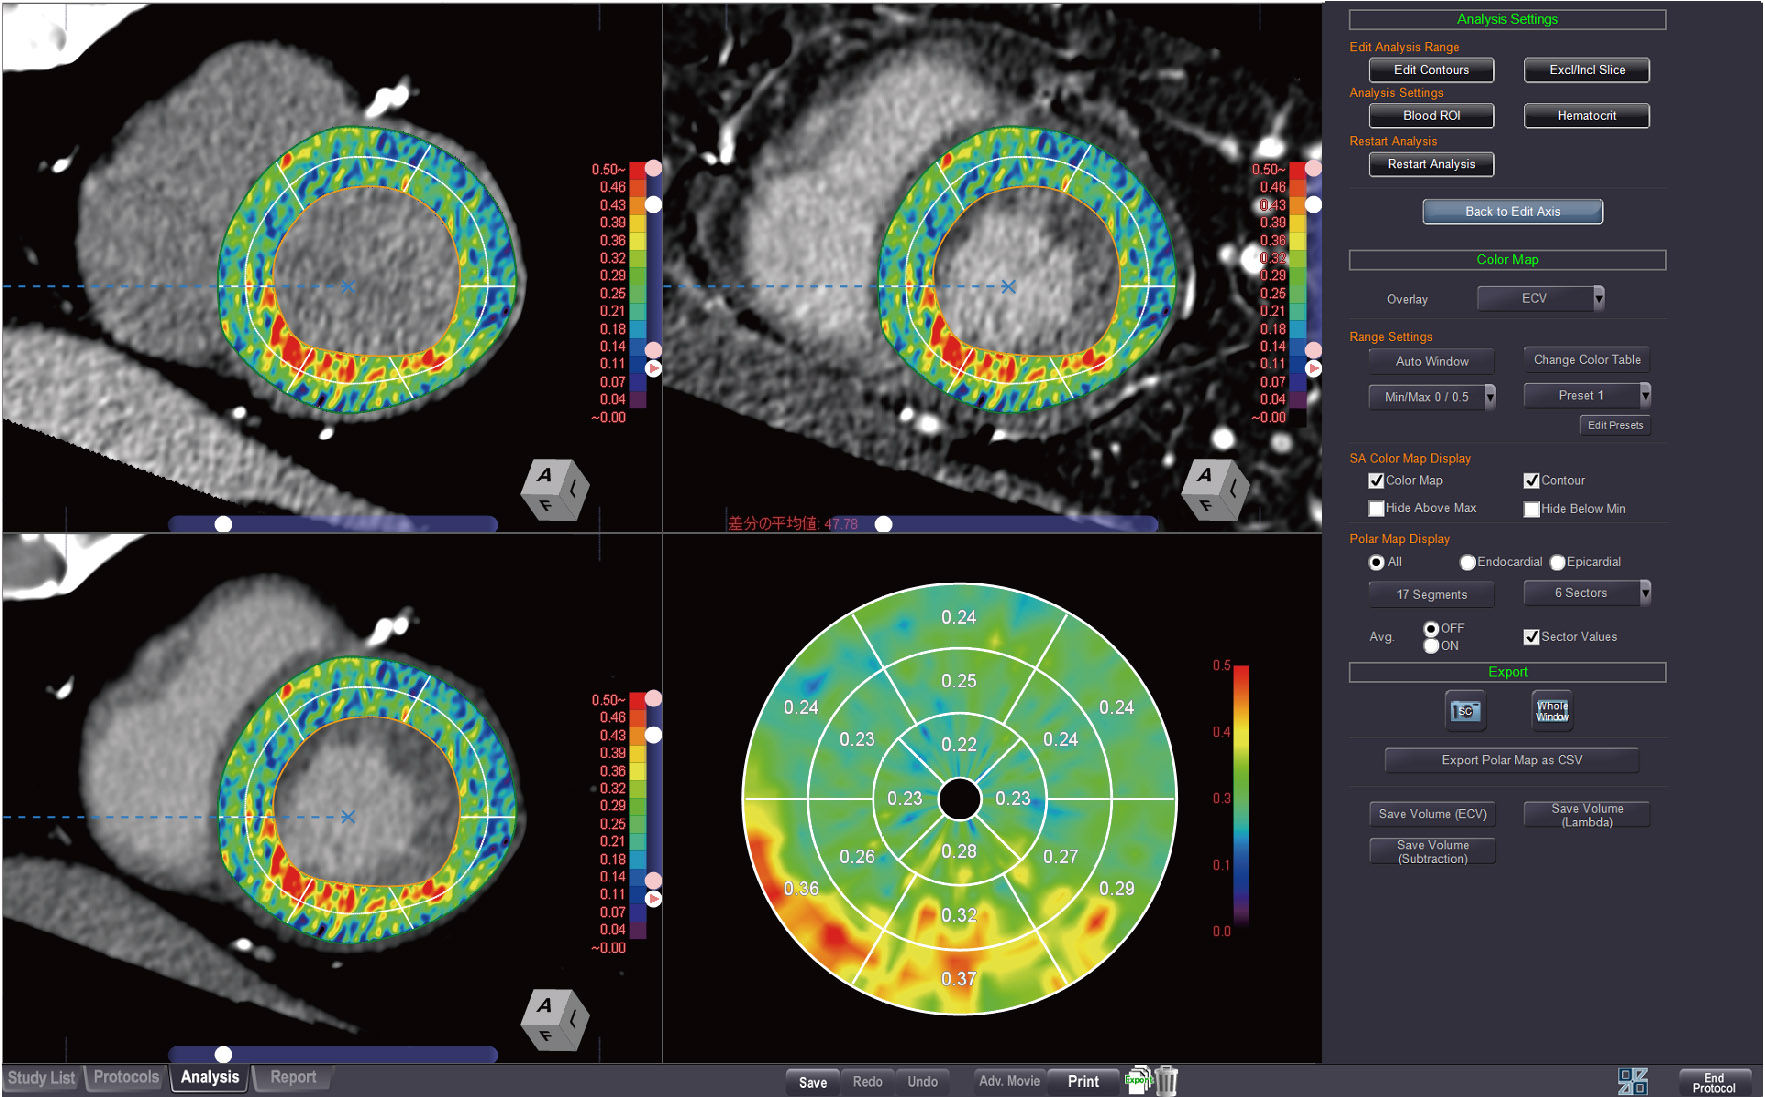

CT MYOCARDIAL ECV ANALYSIS

This protocol calculates myocardial extracelluar volume (ECV) and shows color maps on the myocardium and polar maps.